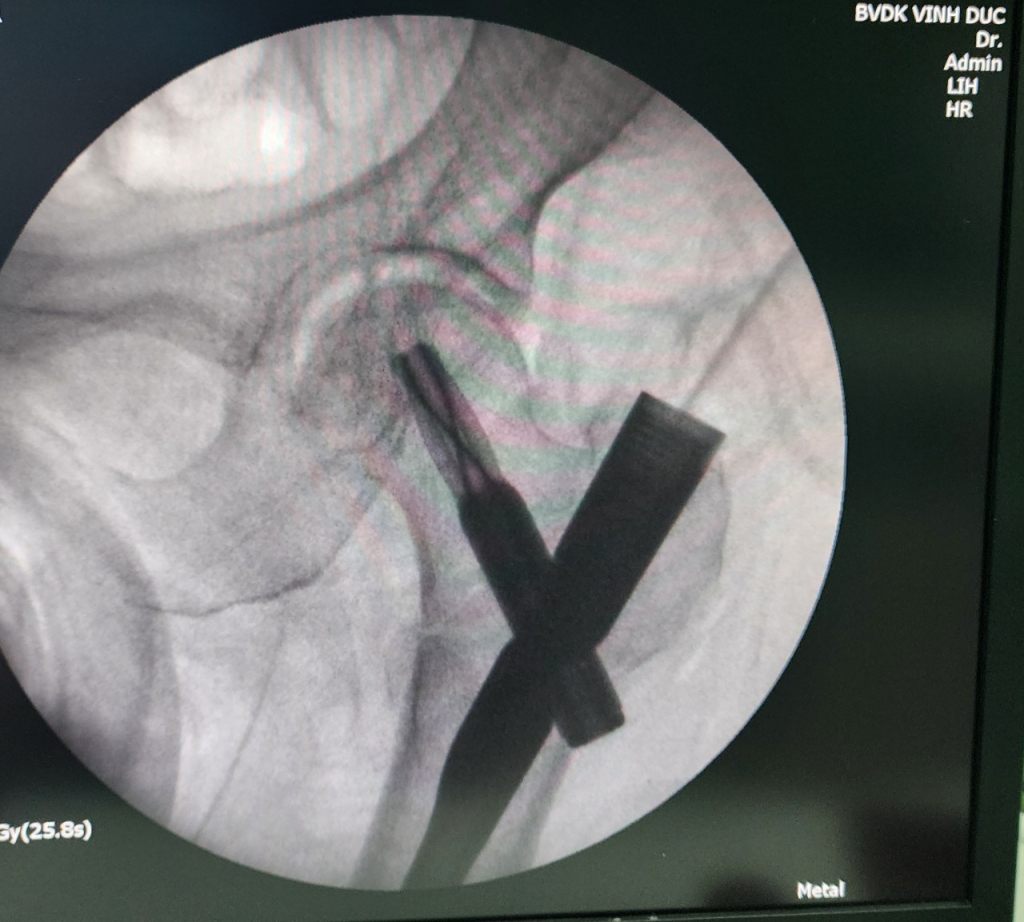

Bệnh viện đa khoa Vĩnh Đức vừa tiếp nhận trường hợp bệnh nhân nữ (81 tuổi, quê Quảng Ngãi) bị gãy liên mẫu chuyển xương đùi sau khi trượt ngã tại nhà. Với tiền sử tăng huyết áp, đái tháo đường và bệnh lý thiếu máu cơ tim Bệnh Viện Đa khoa Vĩnh Đức điều trị thường quy bằng phương pháp phẫu thuật hiện đại không mở ổ gãy sử dụng đinh PFNA dưới màng hình tăng sáng. Người nhà nhanh chóng thuê xe đưa bệnh nhân từ Quảng Ngãi ra Quảng Nam để được điều trị. Sau 2h di chuyển, 1h để làm các xét nghiệm cần thiết, Bệnh nhân đã được tiến hành hội chẩn chuyên môn toàn viện để đánh giá mức độ an toàn của ca phẫu thuật và đưa ra phương án điều trị hiệu quả nhất. Dưới sự phối hợp liên chuyên khoa gồm Khoa Ngoại Chấn thương chỉnh hình; Khoa Tim mạch và Khoa gây mê hồi sức, ngay trong ngày bệnh nhân được tiến hành phẫu thuật kết hợp xương bằng kỹ thuật xâm lấn tối thiểu, sử dụng đinh nội tủy đầu trên xương đùi thế hệ mới (PFNA). Thời gian phẫu thuật chưa đến 30 phút, ngay sau phẫu thuật 4h bệnh nhân có thể cử động chân gãy, sau 1 ngày có thể ngồi dậy và sau 2 ngày tập phục hồi chức năng đi lại dưới hỗ trợ khung tập đi . Bệnh nhân được xuất viện trở về Quảng ngãi sau 5 ngày nằm viện với niềm vui và phấn khởi của bệnh nhân và gia đình.

Nói về kỹ thuật này, BSCKII. Trương Quang Nhân – Phó Khoa Ngoại Chấn thương chỉnh hình Bệnh viện Đa Khoa Vĩnh Đức, Trưởng ekip phẫu thuật cho biết: “Kết hợp xương gãy liên mấu chuyển bằng đinh nội tuỷ đầu trên xương đùi là kỹ thuật mới, đã được áp dụng và thu được nhiều kết quả tích cực ở các trung tâm chấn thương lớn ở TP HCM, Huế, Hà Nội … Tại Bệnh viện Đa khoa Vĩnh Đức. Phương pháp này đã được thực hiện thường quy hơn 5 năm, phương pháp phẫu thuật ít xâm lấn này có những ưu điểm vượt trội so với các phương pháp khác như: đường mổ nhỏ, xâm nhập tối thiểu, giảm mất máu, kết hợp ổ gãy vững, bệnh nhân vận động sớm, điều trị tốt cho loại gãy vững và không vững, gãy liên mấu chuyển kết hợp gãy dưới mấu chuyển hay thân xương đùi. Do đó bệnh nhân có thể sớm trở lại vận động, đi lại, tránh những biến chứng do bất động như: viêm phổi, nhiễm trùng đường tiểu, huyết khối tĩnh mạch, loét tì đè, tử vong…”

“Ngày nay, với sự trang bị và hỗ trợ của các máy móc hiện đại trong phẫu thuật như: cánh tay tăng sáng truyền hình trong mổ ( C- Arm), Bàn nắn kéo chỉnh hình, Ctscaner xương dựng hình. Với Ekip phẫu thuật được đào tạo chuyên nghiệp thì phương pháp phẫu thuật điều trị gãy xương không mở ổ gãy nói chung và gãy liên mấu chuyển xương đùi bằng đinh nội tủi PFNA nói riêng được thực hiện thường quy tại Bệnh viện Đa Khoa Vĩnh Đức đem lại nhiều kết quả rất tốt, giúp cho bệnh nhân tại Quảng Nam và các vùng lân cận được điều trị bằng các phương pháp hiện đại tương đương với các tỉnh thành phố lớn trong và ngoài nước” Bác sĩ Nhân cho biết thêm.